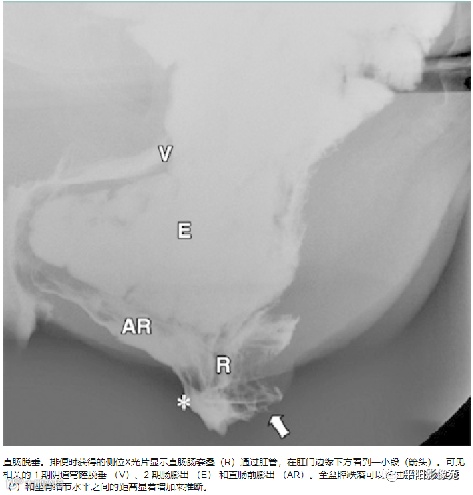

排粪造影

直肠壁部分或全层向下移位,称为直肠脱垂(rectal prolapse)

直肠壁部分下移,即直肠黏膜下移,称黏膜脱垂或不完全脱垂

直肠壁全层下移称完全脱垂

排便造影钡(x射线)排便造影或排便直肠造影是诊断排便障碍的公认临床

工具

。

钡排粪造影实时评估直肠壁形态、盆底运动和排空。